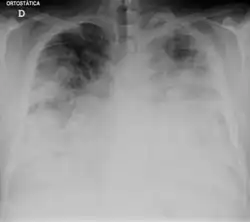

Chest X-ray of a severe case of legionellosis upon admission to the emergency department | |

Laboratory tests may show that kidney functions, liver functions, and electrolyte levels are abnormal, which may include low sodium in the blood. Chest X-rays often show pneumonia with consolidation in the bottom portion of both lungs. Distinguishing Legionnaires' disease from other types of pneumonia by symptoms or radiologic findings alone is difficult; other tests are required for definitive diagnosis.